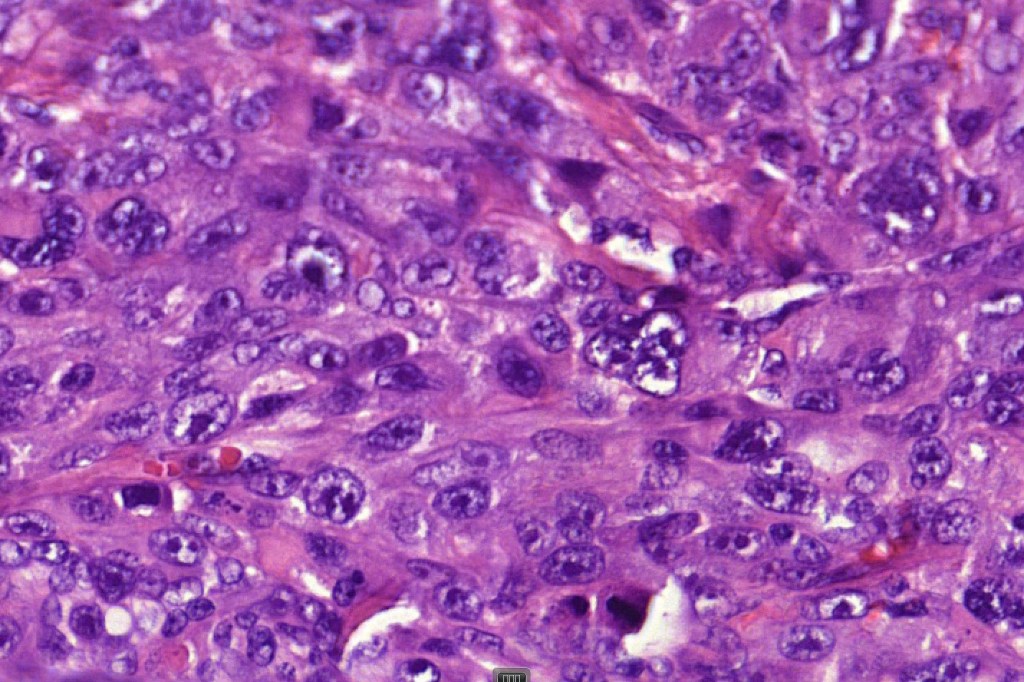

These are very rare variants of amelanotic or virtually amelanotic melanoma where a primary melanoma or a metastasis shows partial (DN) or complete loss (UN) of recognizable histological and immunohistochemical features. The histology may lead the pathologists to consider lymphoma, sarcoma, anaplastic carcinoma or a small cell tumor. Some examples of rhabdoid melanoma & melanoma with heterologous differentiation probably belong in this category. Ultimately, if there is no identifiable/recognizable primary tumor, diagnosis may only be comfortably made with next-generation sequencing. In the cases presented below, immunohistochemistry was of value in determining the melanoctic nature of the tumor (undifferentiated melanoma).